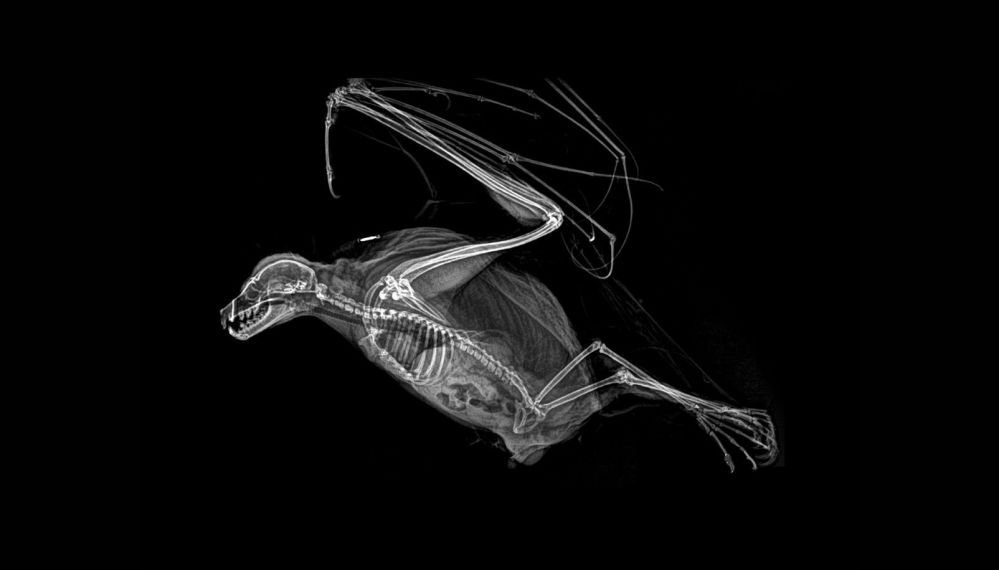

ABD'nin Oregon eyaletinde bulunan bir hayvanat bahçesi, hayvanların rutin sağlık kontrolleri sırasında çekilen X-Ray görüntülerini paylaştı.

Sağlık kontrolleri sırasında bazı hayvanlara röntgen çektiklerini söyleyen hayvanat bahçesi yetkilileri, bu yöntem sayesinde sağlık değerlendirmelerinin daha kolay yapıldığını ifade etti.

Baykuşun X-Ray görüntüsü.